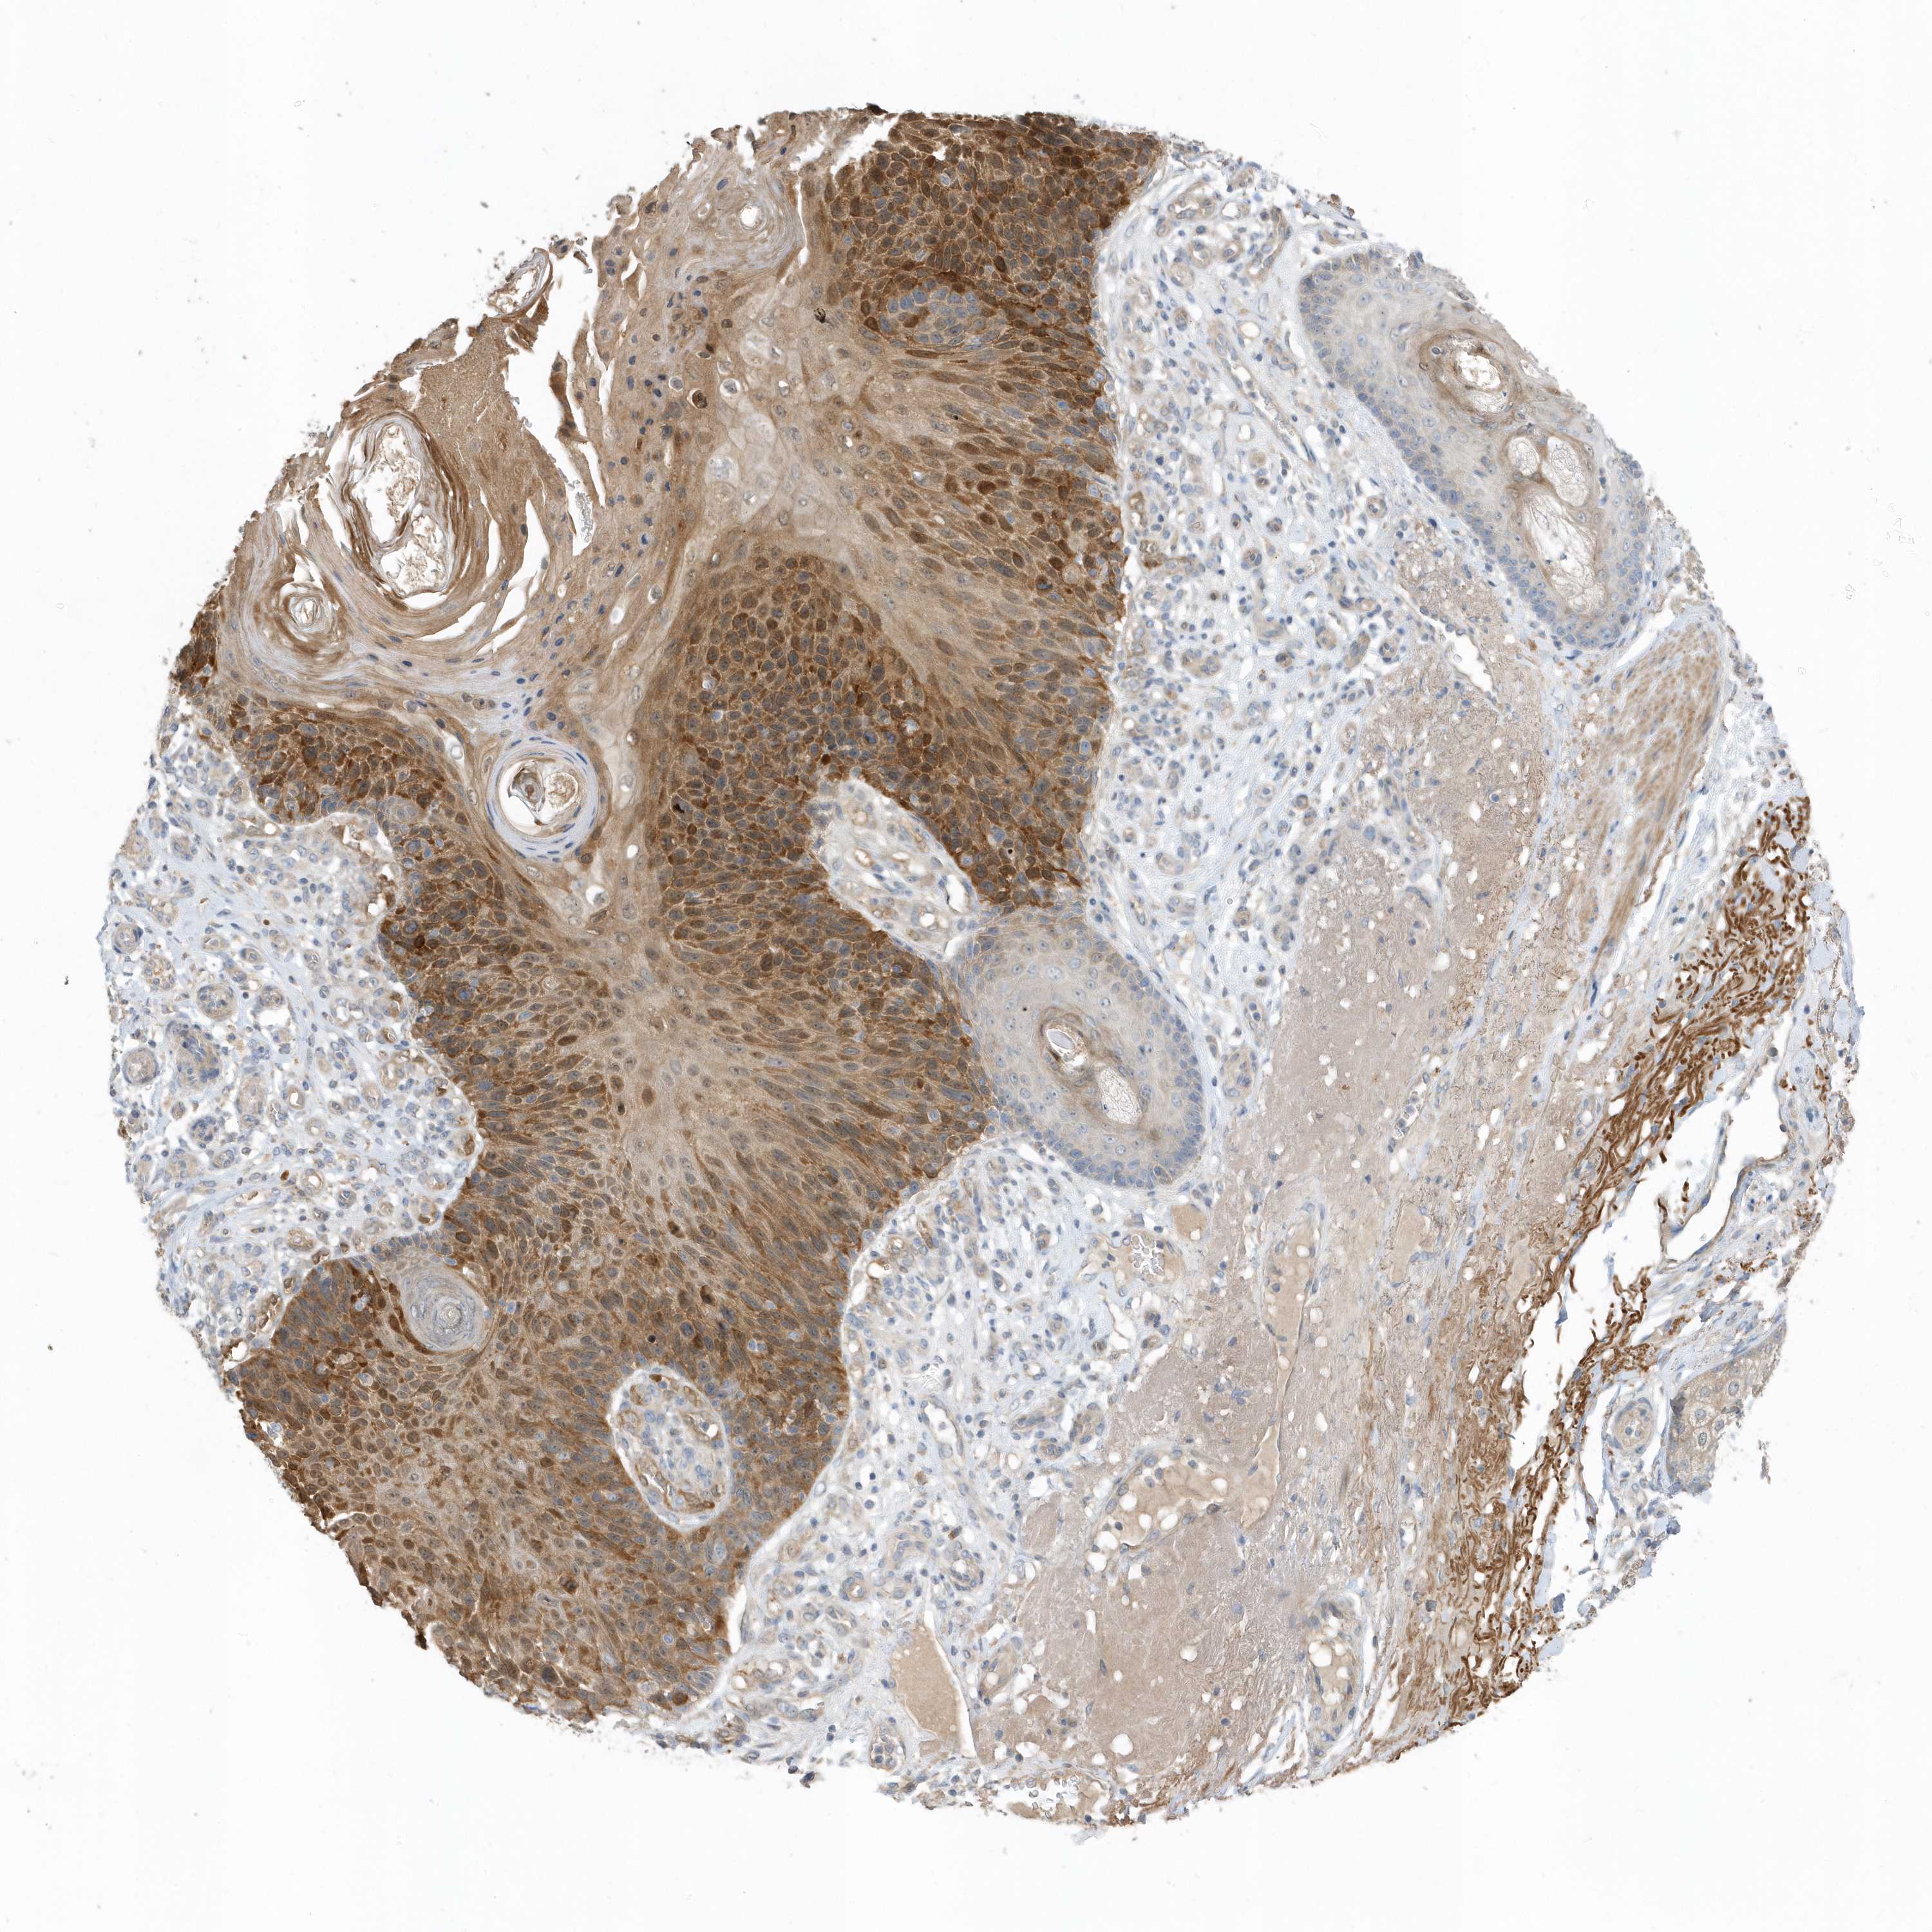

Basal cell and squamous cell cancer

SKIN CANCER - Protein expressioni

A mouse-over function shows sample information and annotation data. Click on an image to view it in a full screen mode. Samples can be filtered based on level of antibody staining by selecting one or several of the following categories: high, medium, low and not detected. The assay and annotation is described here.

Antibody stainingi

Antibody staining in the annotated cell types in the current human tissue is reported as not detected, low, medium, or high, based on conventional immunohistochemistry profiling in selected tissues. This score is based on the combination of the staining intensity and fraction of stained cells.

Each image is clickable and will lead to virtual microscopy that enables deeper exploration of all samples and also displays staining intensity scores, fraction scores and subcellular localization as well as patient and tissue information for each sample.

Antibody HPA035844

Antibody HPA035845

Staining

High

Strong

>75%

Cytoplasmic/membranous

Squamous cell carcinoma, NOS